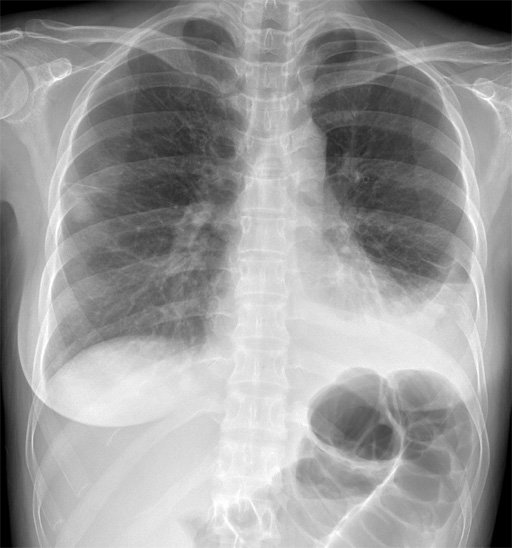

No.84症例2:30歳代女性

• 図1 初診時 胸部X線撮影 PA像